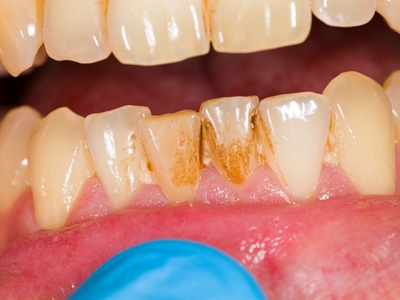

牙龈退缩牙根暴露出现黑斑图

牙龈退缩患者的上排多颗牙齿处的牙龈出现回缩,从而导致牙根外露,外露的牙根上存在黑色的牙菌斑、牙结石,伴有口臭、牙根面敏感等症状。